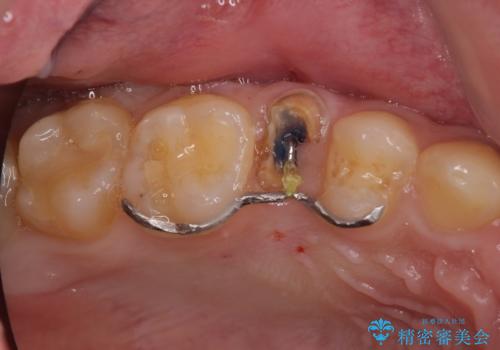

歯を引っ張り出したり、歯肉の手術の経過待ちの間に、患者様のご希望で他の歯の虫歯治療も行いました。

右上もう1本と左上は虫歯治療(セラミックインレー、セラミッククラウン)を行いました。